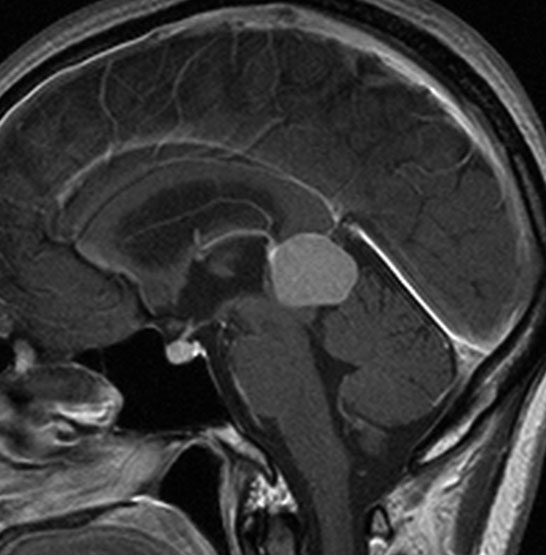

成人女性の松果体細胞腫で充実性腫瘍です。中脳水道が閉塞して軽度の水頭症(頭の中に髄液が溜まる)になってきています。多少凹凸がありますがだいたい楕円形。